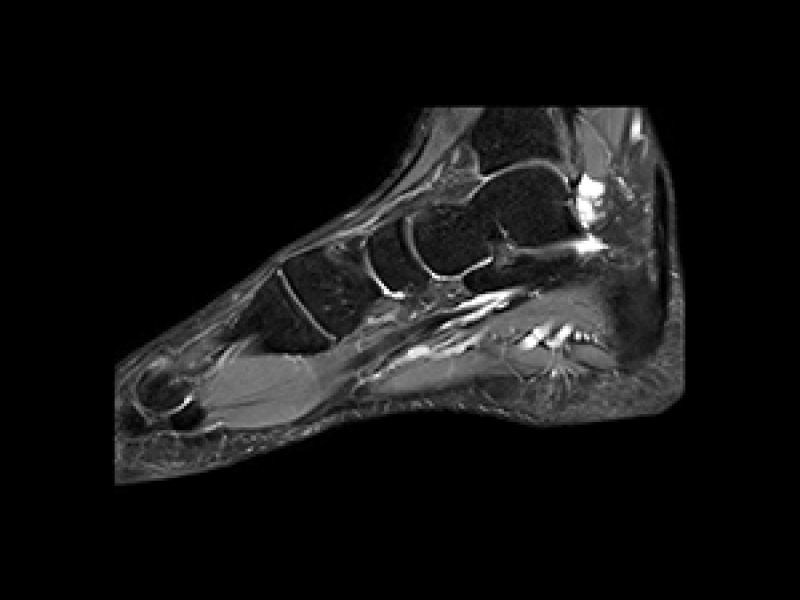

Mūsu klīnikā Teika Plaza, Rīgā, mēs piedāvājam dažādus magnētiskās rezonanses izmeklējumus gan valsts apmaksātus, gan privātus pakalpojumus. Mūsu pakalpojumi ir īpaši piemēroti neiroloģiskiem izmeklējumiem, locītavu izmeklējumiem, iekšējo orgānu analīzēm un daudzām citām diagnostiskām vajadzībām. Ar modernu iekārtu palīdzību mēs veicam izmeklējumus, kas nodrošina augstu precizitāti un atbilstību visām medicīniskajām prasībām.

Mūsu pakalpojumi aptver smadzeņu, mugurkaula, locītavu un iekšējo orgānu izmeklējumus. Mēs sniedzam detalizētus attēlus, kas palīdz ārstiem ātri noteikt diagnozi un izstrādāt efektīvas ārstēšanas metodes.